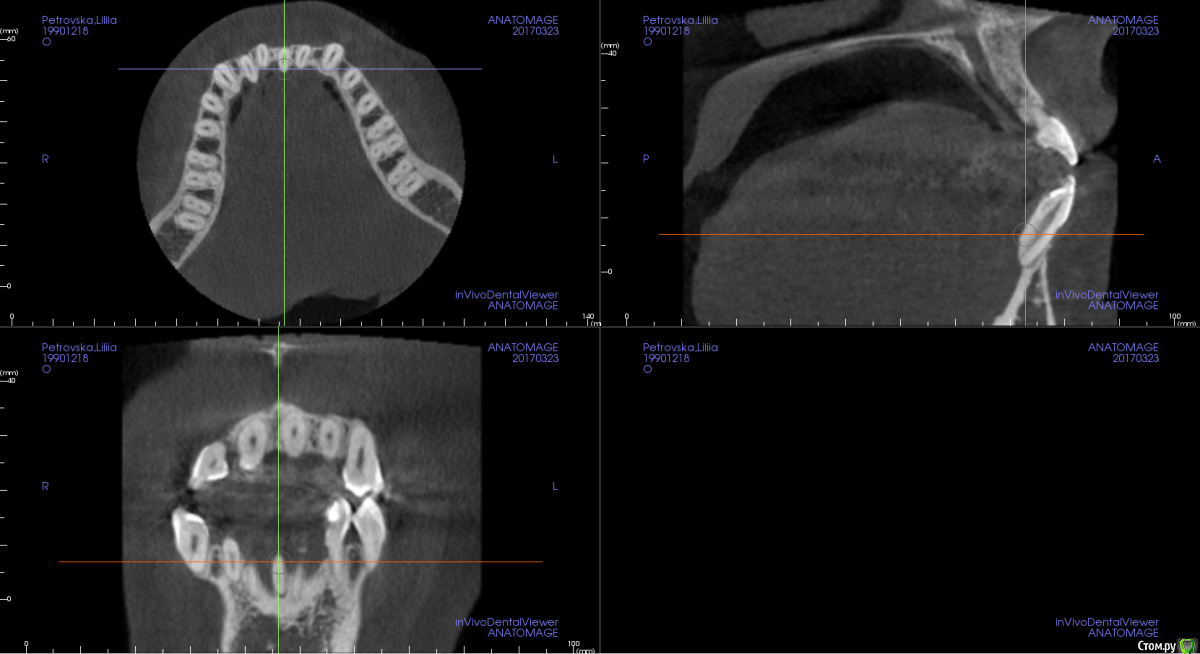

Opdihatop Опубликовано 4 марта, 2017 Поделиться Опубликовано 4 марта, 2017 И снова здравствуйте, коллеги. Вот такой вот случай к рассмотрению. Много лет назад пациентка уже проходила "камуфляжное" лечение. Со слов пациентки оно было закончено с передним открытым прикусом. Сейчас ситуация такая. Пациентка думает над ортохирургией, но меня смущает фронт н/ч. И по снимкам и по ситуации во рту корни 32, 31, 42, 43 зубов фенестрировали лингвальную кортикалку почти на всем протяжении, 33 - вестибулярную. Вопрос вот в чем: что делатьс этими зубами? Возможно ли их поставить на место? Или лучше не трогать, дольше простоят? Ссылка на комментарий

m.d.n Опубликовано 20 марта, 2017 Поделиться Опубликовано 20 марта, 2017 срезы кт покажите . на чем остановились Ссылка на комментарий

Opdihatop Опубликовано 26 марта, 2017 Автор Поделиться Опубликовано 26 марта, 2017 Прошу:313233414243 Ссылка на комментарий